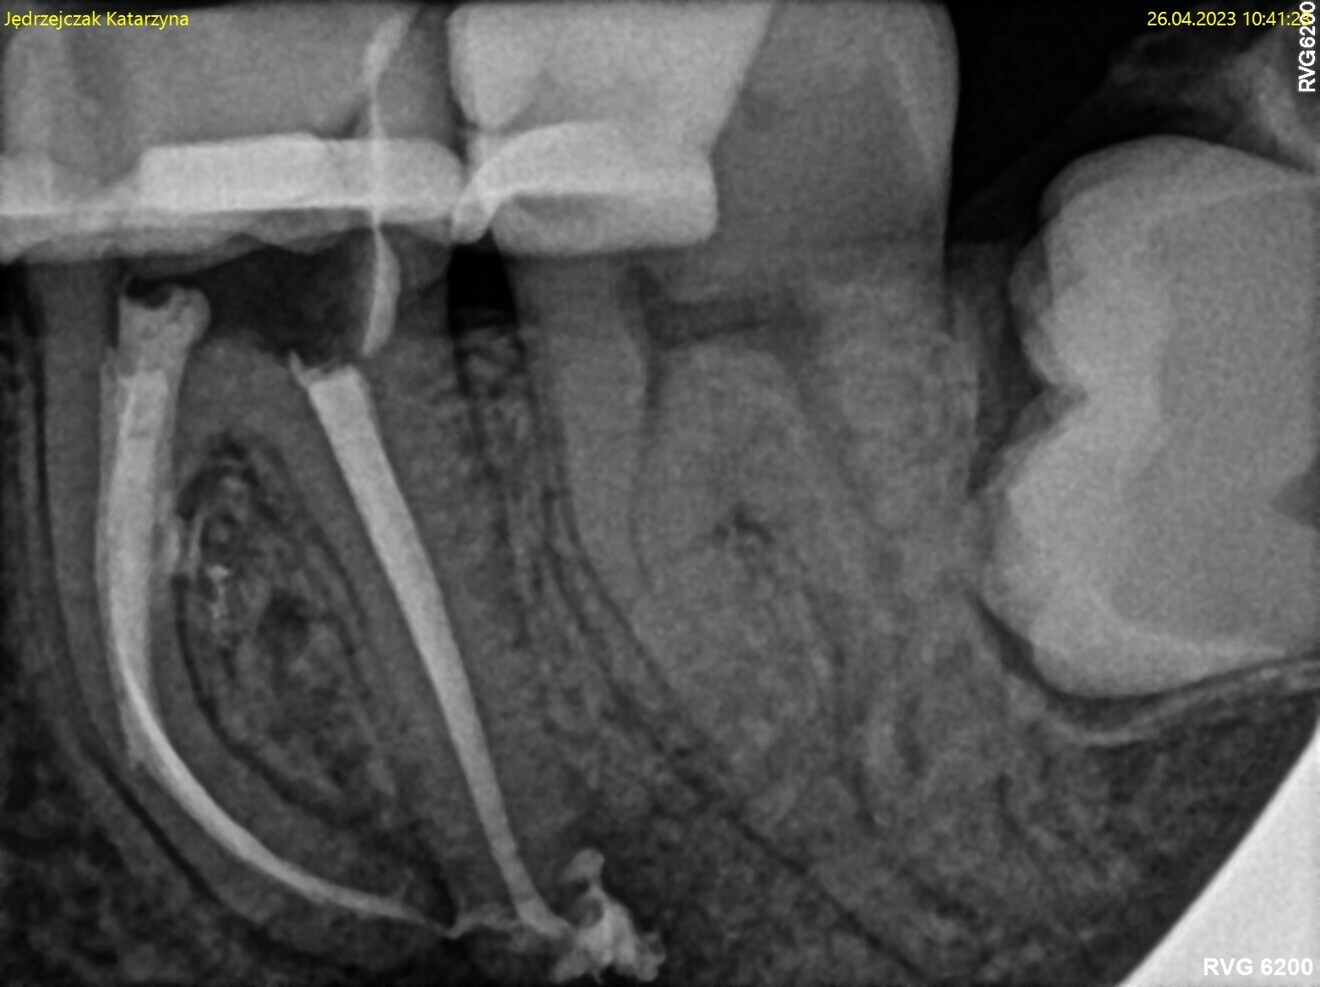

Fig. 1: Pre-op radiograph. Periapical lesion and broken file visible.

The periapical radiograph and the CBCT scan revealed that the file had broken far beyond the curvature in the mesiobuccal canal and below the junction with the mesiolingual canal. Also, a periapical lesion was visible around the apices of the mesial and distal roots (Figs. 1–3). The length of the file was approximately 5 mm. Bypassing the file through the mesiolingual canal would have been a risky procedure because it may have caused the fracture of the second instrument and the obturation may also have been very challenging. Thanks to SWEEPS technology and a bioceramic sealer, an alternative approach could be taken. After administering anaesthesia and placing a dental dam, the temporary restoration was removed (Figs. 4 & 5). The pulp chamber was rinsed with 5.25% sodium hypochlorite and the irrigant activated with ultrasonics. After cleaning the chamber of the tooth, the dental dam and clamp were rinsed with water and dried and flowable dental dam was placed to seal the tooth and enlarge the space in the pulp chamber for the laser-activated irrigation (Fig. 6). Activation was performed with the SkyPulse laser (Fotona). The AutoSWEEPS mode was chosen. The power of activation was set to 1 W. The flat SWEEPS 300/20 fibre tip was used (Fig. 7). The tip was placed slightly below the orifice of the mesiobuccal canal for the majority of the irrigation with sodium hypochlorite. After 120 seconds of activation with sodium hypochlorite, the tip was placed in the pulp chamber to activate the sodium hypochlorite in all the canals simultaneously for 30 seconds. This procedure was continued for 30 minutes. Only the distal canal was shaped with rotary files, up to size 40/.04. Both mesial canals remained the same size as they were before the file broke during the primary treatment. Finally, the canals were flushed with EDTA activated with AutoSWEEPS at a power of 0.4 W, and sodium hypochlorite was activated for three cycles with AutoSWEEPS at a power of 0.6 W and with a 30-second break for the resting phase. The irrigant flow between the mesiobuccal and mesiolingual canals was rapid, indicating that obturation could be performed.